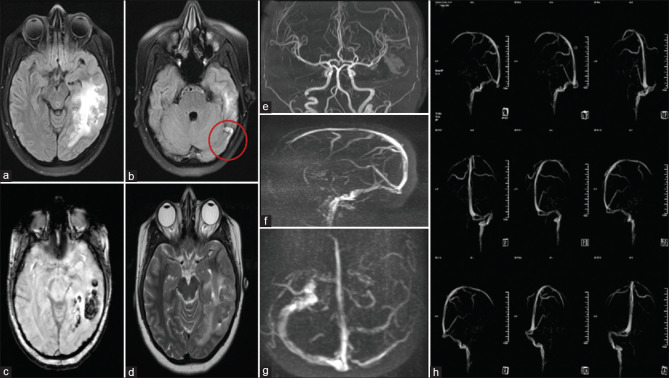

Arterial and Venous Infarcts: Dual Phenotypes of Dual Heterozygous MTHFR Gene Mutation.

动脉和静脉梗死:双杂合MTHFR基因突变的双重表型。